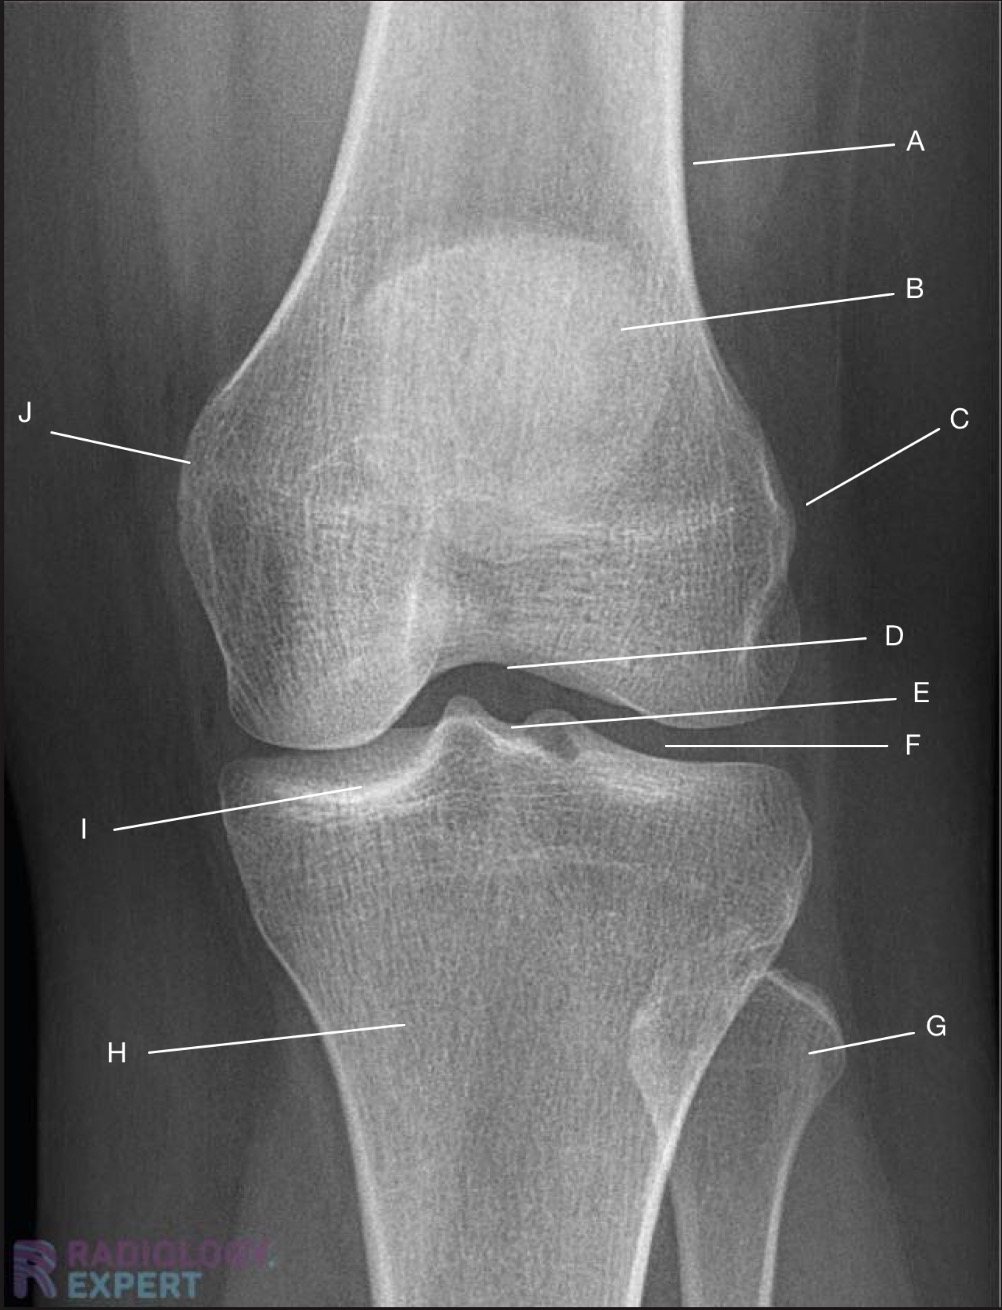

Name the projection.

Should it be repeated, if so why?

AP Knee

No

Label the image

A) Femur

B) Patella

C) Lateral femoral epicondyle

D) Intercondylar fossa

E) Intercondylar eminence

F) Femorotibial joint

G) Fibula

H) Tibia

I) Tibial condylar margin

J) Medial femoral epicondyle